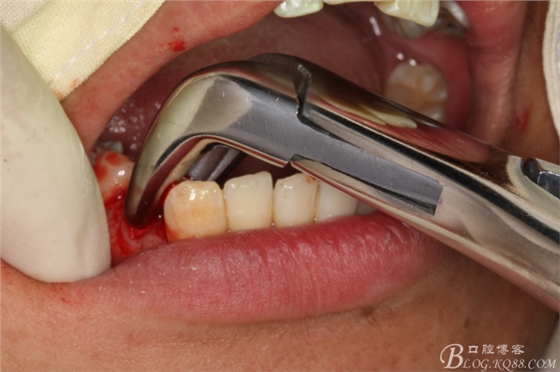

圖23.放置牙鉗拔除

圖24.拔除44

圖25.同樣的方法拔除37.

圖26.拔除34

圖27拔除的34、37、44、47.